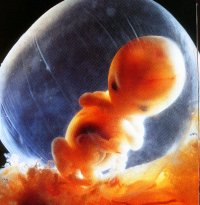

0 - 16 Week Development

Six weeks after conception, the baby is an identifiable human form.  The heart has been beating for three weeks and brain waves are detectable.  You can see the blood being pumped into the baby's heart.  The blood is flowing from the placenta through the umbilical cord into the liver.  The baby's ear, eyes, and the tiny hands and feet are clearly noticeable.